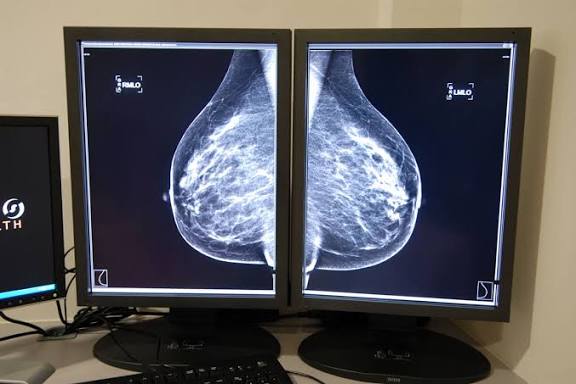

Mamografía con IA

Hoy, por primera vez, hay evidencia sólida de que una herramienta puede reducir ese margen de error sin crear nuevos problemas. No con promesas futuristas ni discursos de Silicon Valley, sino con datos clínicos en condiciones reales. Un ensayo con más de 100.000 mujeres sugiere que la inteligencia artificial puede ayudar a detectar el cáncer de mama antes de que se vuelva más agresivo, sin aumentar falsos positivos ni desplazar al médico.

El estudio, liderado por la radióloga Kristina Lång desde la Universidad de Lund, incluyó a más de 100.000 mujeres en Suecia. No fue un piloto de laboratorio, sino un ensayo aleatorizado dentro de un programa nacional de cribado.

● La detección con apoyo de IA identificó el 81% de los cánceres durante el cribado.

● Los cánceres de intervalo se redujeron un 12%: de 1.76 a 1.55 por cada 1,000 mujeres.

● Sensibilidad del 80.5% y especificidad del 98.5%.

Sin incremento relevante de falsos positivos.

En términos simples: más cánceres detectadosantes, menos tumores agresivos apareciendo tarde, y sin someter a más mujeres a alarmas innecesarias.

El algoritmo utilizado desarrollado por ScreenPoint Medical fue entrenado con más de 200,000 mamografías de 10 países y funciona como un sistema de triaje. Asigna un puntaje de riesgo del 1 al 10: los estudios de bajo riesgo requieren una sola lectura; los de mayor riesgo, doble lectura humana.